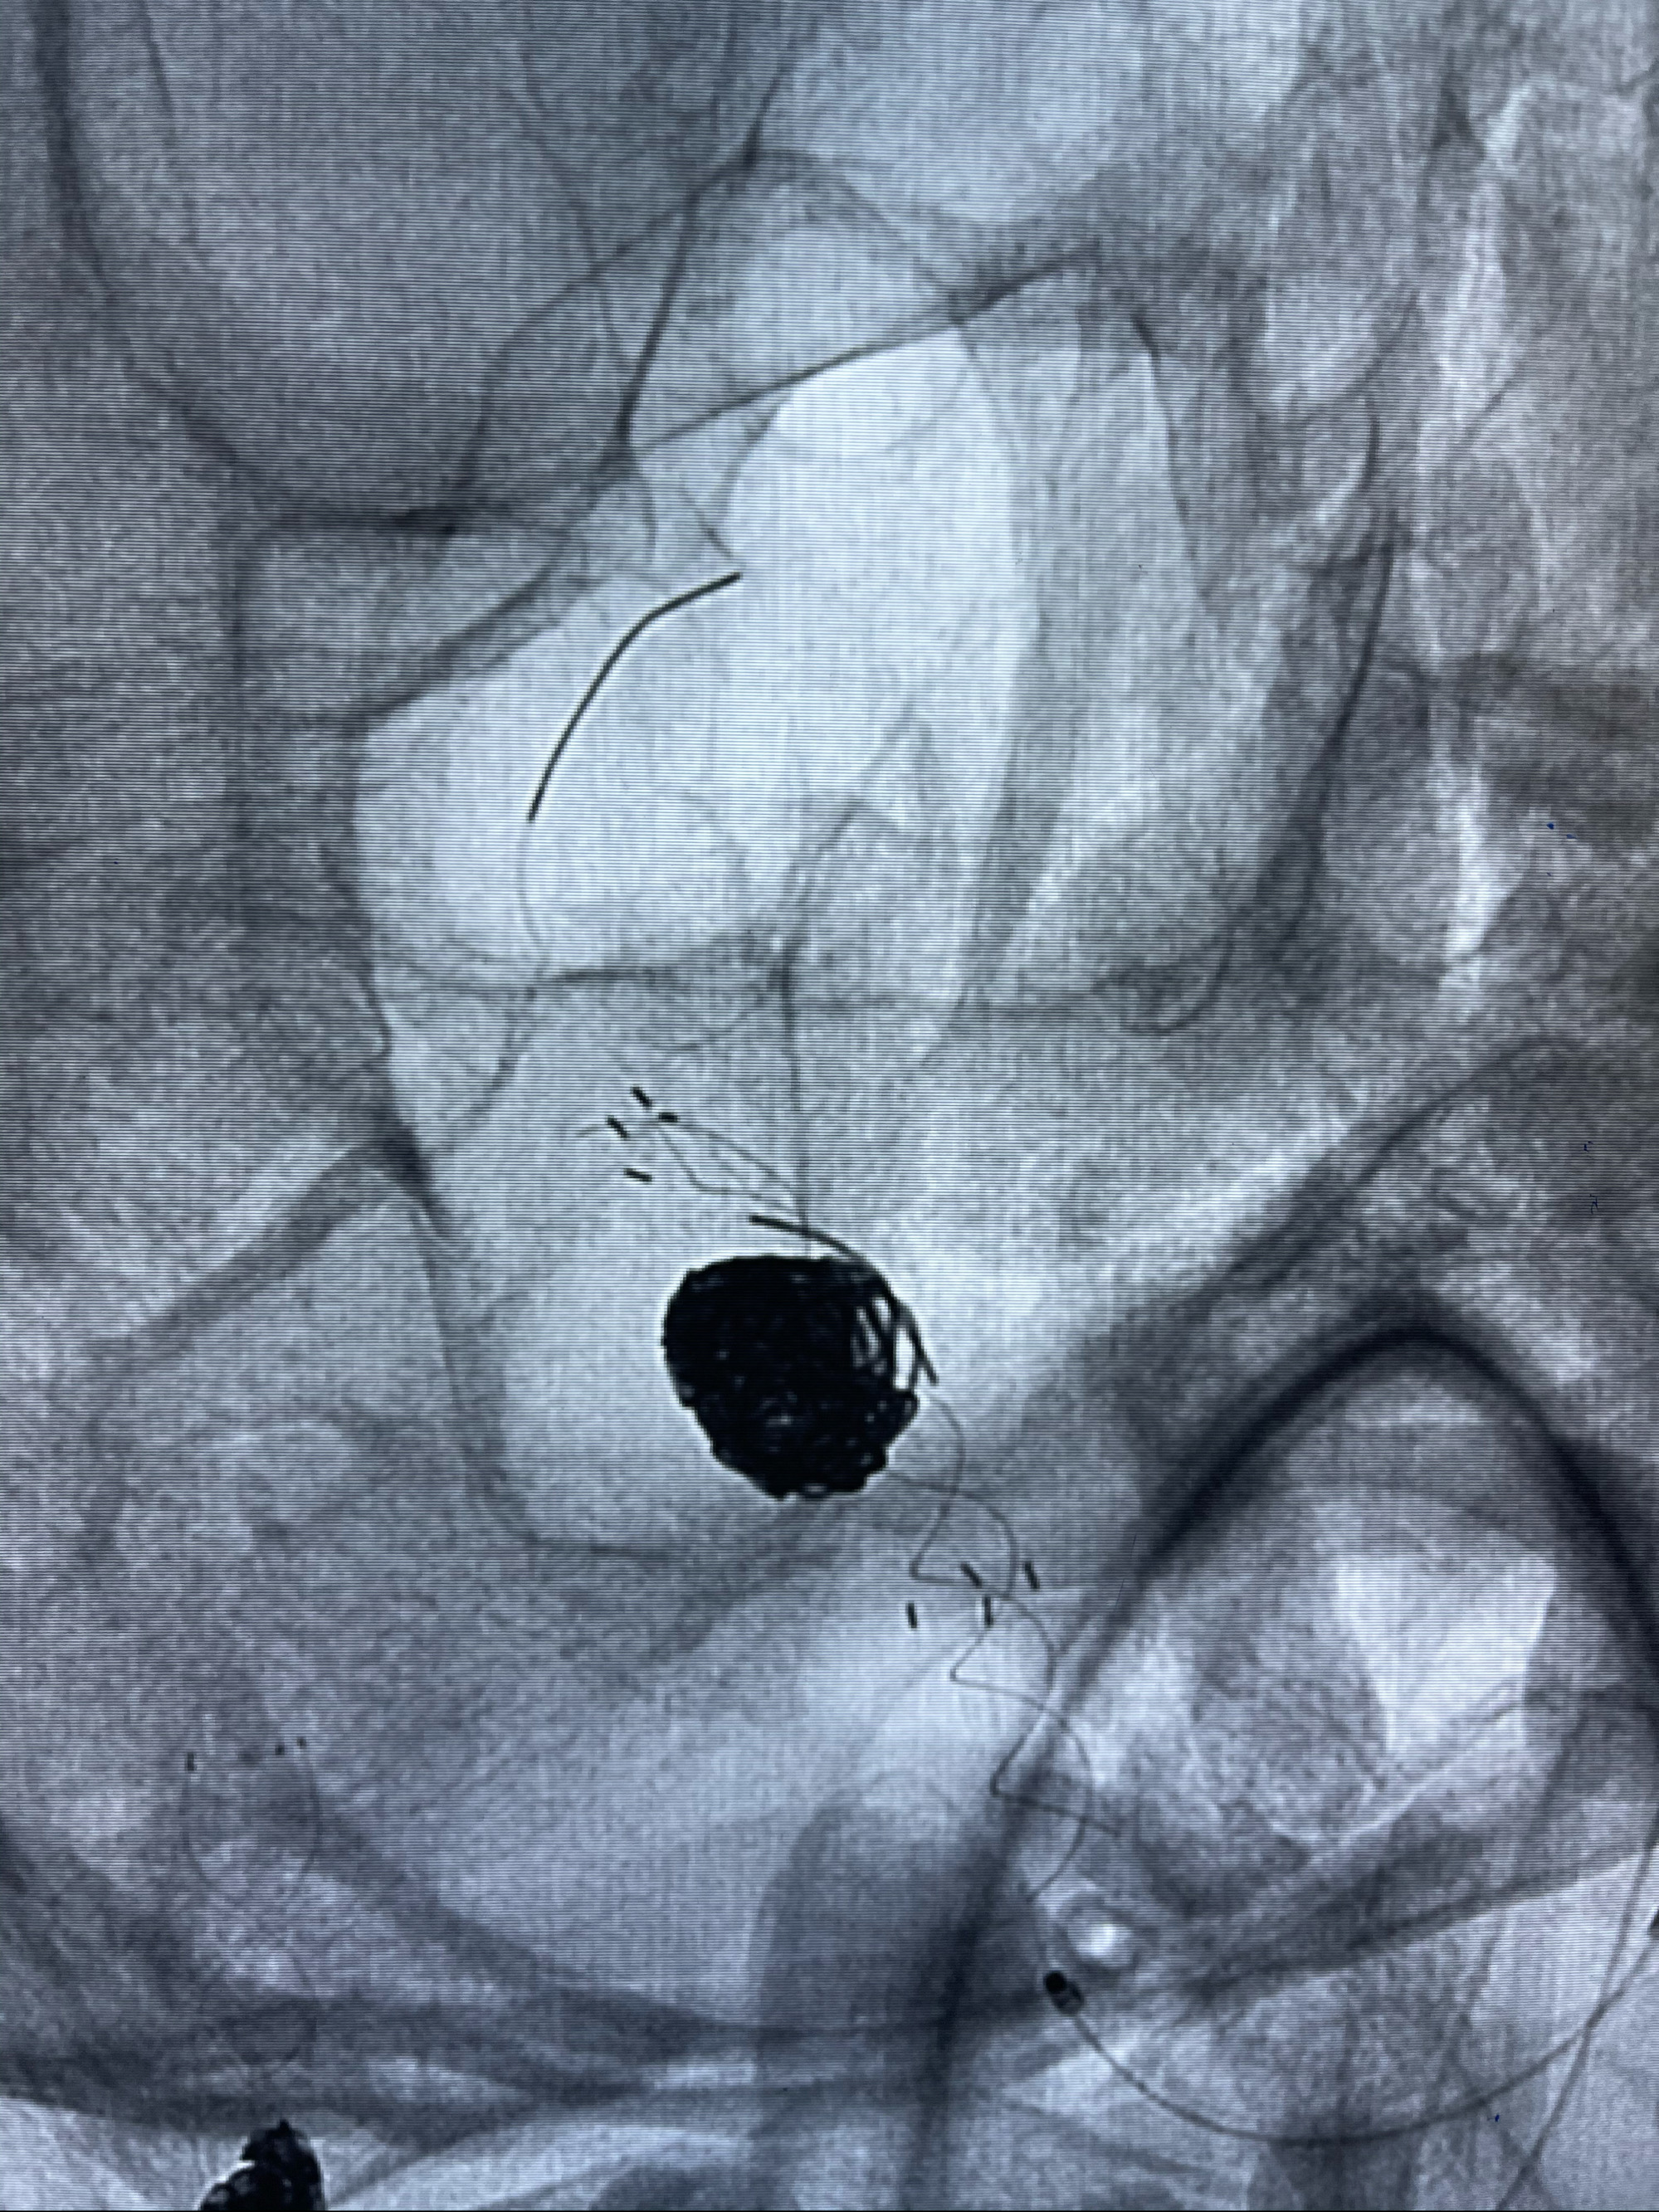

Eterprise4.0-23mm支架导管到位

Echelon10 45°角微导管塑形后到位

支架到位

支架释放,透视下